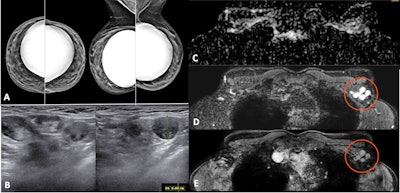

- In patients without breast cancer history, incidental unilateral axillary lymphadenopathy after COVID-19 vaccination coupled with ipsilateral suspicious findings in the breast at any imaging modality should be managed according to clinical practice, including biopsy when appropriate.

- In patients with personal breast cancer history, lymphadenopathy after vaccination should be interpreted considering the time since vaccination and overall nodal metastatic risk (cancer type, location, stage, etc.). For patients at low risk of axillary or supraclavicular nodal metastases in whom the lymphadenopathy is much more likely due to the vaccination than to the underlying neoplasm (considering time frame, pain, type, and location of cancer), a cautious management strategy without default follow-up imaging is appropriate. Short-interval follow-up imaging with ultrasonography (with at least a 12-week delay) may be performed in patients with higher risk of metastatic lymphadenopathy (e.g., breast cancer, head and neck cancer, upper extremity/trunk melanoma, or lymphoma). Node biopsy should be considered in the setting of high nodal metastatic risk when immediate histopathologic confirmation is necessary for timely patient management.